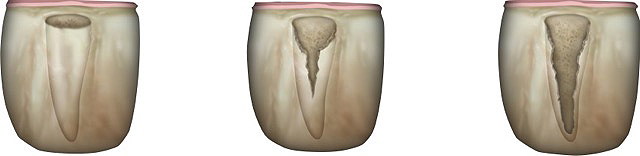

Fig 5. Sagittal cross-sections of CBCT images depicting Grade I (Left), Grade II (Center), and Grade III (Right) sockets. Note the level of the buccal plate relative to the cementoenamel junction that is elucidated by this cross-cut.

Figure 5